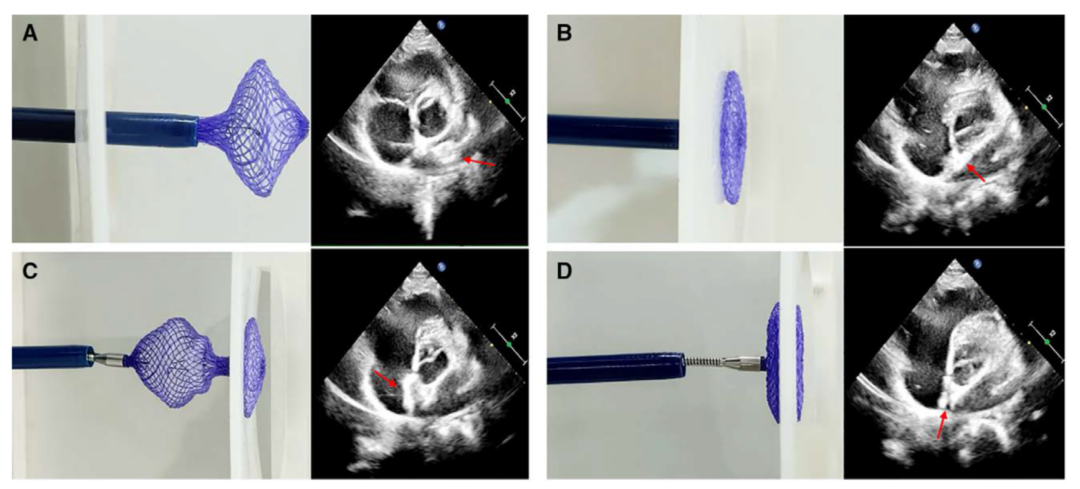

2025年全球首个生物可降解PFO封堵器的前瞻性、多中心、随机对照临床试验结果在Circulation杂志发表,标志着中国在PFO治疗领域实现了从"跟跑"到"领跑"的跨越[3]。中国原研的MemoSorb®生物可降解PFO封堵器采用独特的成型锁定设计保证封堵器植入后双盘紧密贴合,保证支撑稳定且不移位(图1)。临床试验数据显示,可降解PFO封堵器组87例患者(90.63%)实现成功封堵,镍钛合金PFO封堵器组86例患者(91.49%)实现成功封堵,证实可降解PFO封堵器在封堵疗效方面不劣于镍钛合金封堵器。最重要的差异是可降解封堵器植入后24个月内在超声心动图上的结构完全消失,且封堵器植入处的房间隔无增厚,达到影像学的生理性修复。

图1. MemoSorb可降解PFO封堵器展开过程的体外和超声示意图